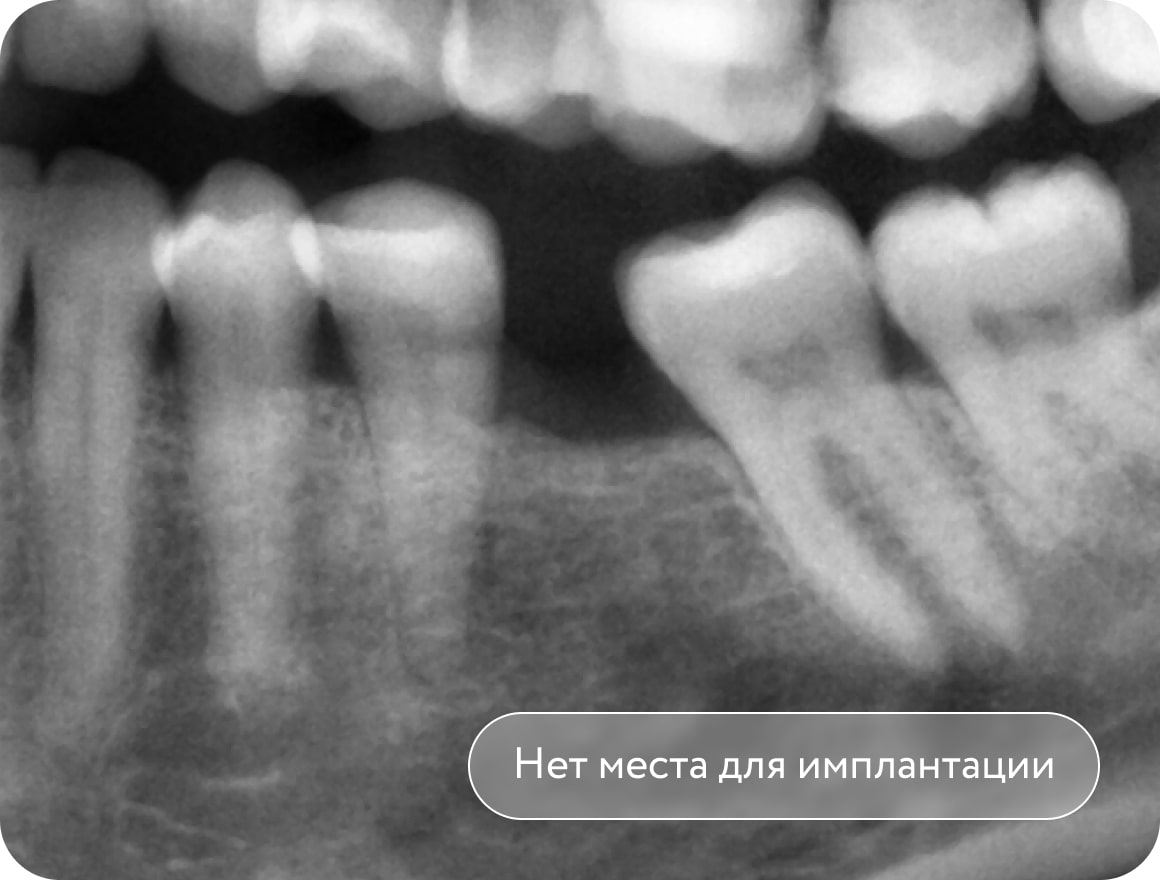

Отсутствие 1 моляра - “шестерки”. Зуб мудрости прорезался и наклонил 2 моляр

(седьмой зуб) в сторону отсутствующего 6 зуба. Недостаток места для имплантации